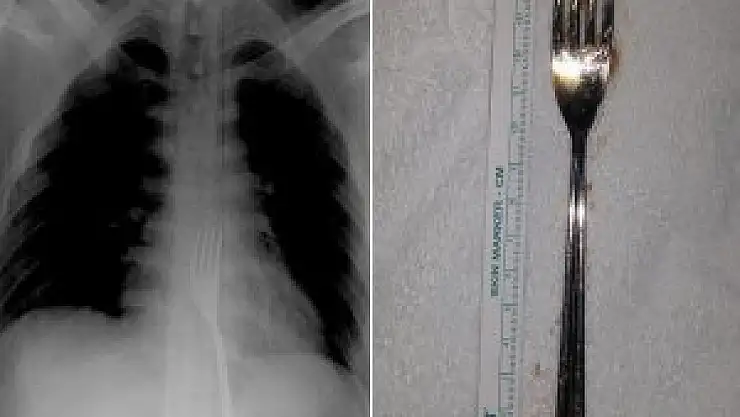

Çekilen röntgen filmlerinde, 15 santimetrelik çatalın midede olduğu görüldü. Metal çatal, O.A'nın midesinden ameliyatla çıkarıldı. O.A, taburcu edildi.